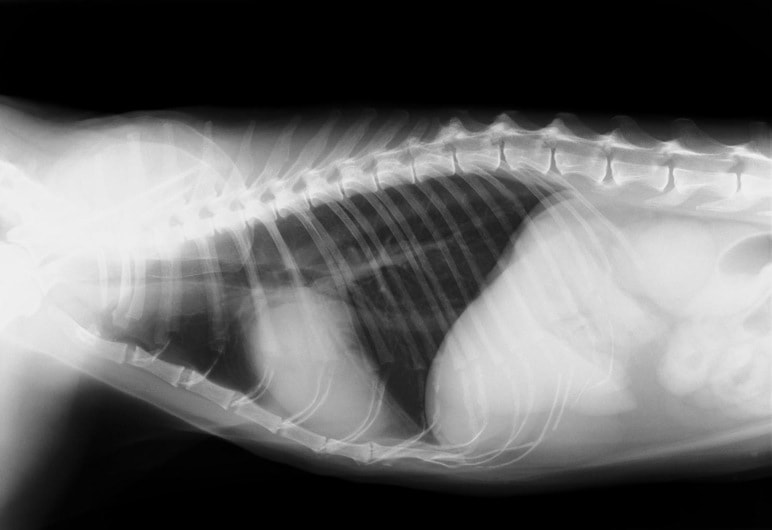

D:胸部レントゲン写真 正面像

E:胸部レントゲン写真 側面像

左側胸壁心尖部領域を最強点とするLevine 5/6の収縮期性心雑音が聴取された。

胸部レントゲン検査において重度の心拡大と肺水腫が認められた。超音波検査では、重度の僧帽弁閉鎖不全症、三尖弁閉鎖不全症、中程度の大動脈弁閉鎖不全症を合併していることが判明した。三尖弁逆流速度から肺高血圧症が示唆された。

ACE阻害薬、ピモベンダン、硝酸イソソルビド徐放剤、ベラプロストナトリウム、利尿剤としてフロセミドとスピロノラクトンを用いて治療を行った。